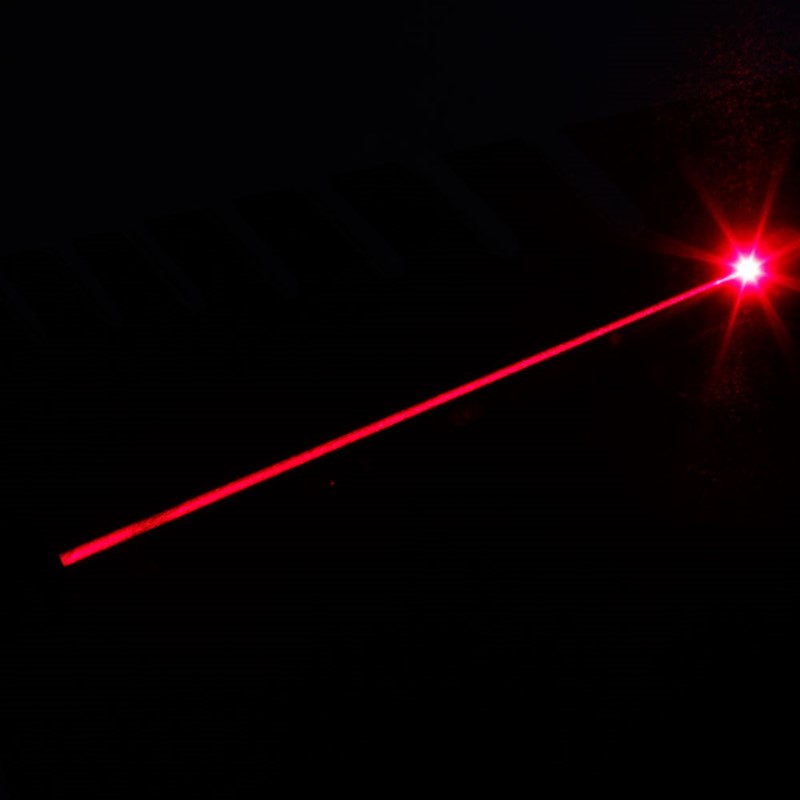

Iza formule C3N4–MnO2 krije se nanočestica, ili bolje rečeno nanopločica, koja se sastoji od nanometar debelog sloja međusobno povezanih atoma ugljika i dušika (C3N4) za koje su vezane molekule manganova dioksida (MnO2). Kada se te nanočestice unesu u tkivo, one se djelovanjem glutationa (GSH), kojeg ima naročito mnogo u tumorskom tkivu, reduciraju u čestice C3N4–Mn(II). One su vrlo reaktivne, no samo ako elektron prijeđe s atoma dušika na atom mangana – što to se događa kada ih se osvijetli crvenom svjetlošću lasera, tj. elektromagnetskim zračenjem valne duljine 660 nm. U takvom, pobuđenom stanju, nanočestica C3N4+–Mn(I) veže atome vodika (⸱H) iz molekule vode (H:OH) pri čemu nastaju radikali ⸱OH. Oni reagiraju s molekulama nezasićenih masnih kiselina što na kraju dovodi do smrti stanice. (Ista se nanočestica može osvijetliti više puta jer se regenerira reakcijom s pirogrožđanom kiselinom, Pyr, koja prelazi u mliječnu kiselinu, Lac.)

Jasno je: do uništenja stanica može doći samo kada se tkivo osvijetli i tamo gdje se osvijetli. Riječ je dakle o vrlo jednostavnom sredstvu za uništavanje tumorskog tkiva koje je usto manje štetno i neugodno za pacijenta od ionizirajućeg zračenja ili kirurškog noža. No koliko je djelotvorno?

Na to je pitanje odgovorio pokus na miševima. Sedam dana nakon što su im usađene tumorske stanice (HeLa) injektiran je nanočestični lijek, a nakon 24 sata mjesto rasta tumora bilo je deset minuta osvjetljeno crvenom svjetlošću. Tumor je počeo rasti, a onda se osmog dana dogodio presudni trenutak: u kontrolnoj skupini tumor je rastao i dalje dok se u skupini liječenoj fotodinamičkom terapijom počeo smanjivati. Petnaestog dana nakon početka terapije pokazao se njezin uspjeh u punom sjaju: dok je u kontrolnoj skupini masa tumora iznosila prosječno 400 mg, u skupini liječenoj nanočesticama C3N4–MnO2 i crvenim svjetlom masa tumora bila je četiri puta manja – 100 mg. Zanimljivo je da su dobri rezultati postignuti obim vrstama nanočestica, i C3N4–MnO2 i C3N4–Mn, no ipak bolje prvima nego drugima.